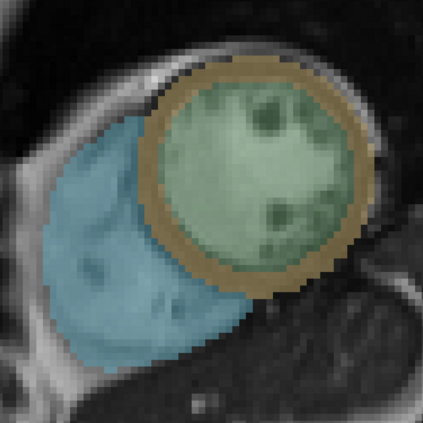

In cardiac magnetic resonance (CMR) imaging, a 3D high-resolution segmentation of the heart is essential for detailed description of its anatomical structures. However, due to the limit of acquisition duration and respiratory/cardiac motion, stacks of multi-slice 2D images are acquired in clinical routine. The segmentation of these images provides a low-resolution representation of cardiac anatomy, which may contain artefacts caused by motion. Here we propose a novel latent optimisation framework that jointly performs motion correction and super resolution for cardiac image segmentations. Given a low-resolution segmentation as input, the framework accounts for inter-slice motion in cardiac MR imaging and super-resolves the input into a high-resolution segmentation consistent with input. A multi-view loss is incorporated to leverage information from both short-axis view and long-axis view of cardiac imaging. To solve the inverse problem, iterative optimisation is performed in a latent space, which ensures the anatomical plausibility. This alleviates the need of paired low-resolution and high-resolution images for supervised learning. Experiments on two cardiac MR datasets show that the proposed framework achieves high performance, comparable to state-of-the-art super-resolution approaches and with better cross-domain generalisability and anatomical plausibility.